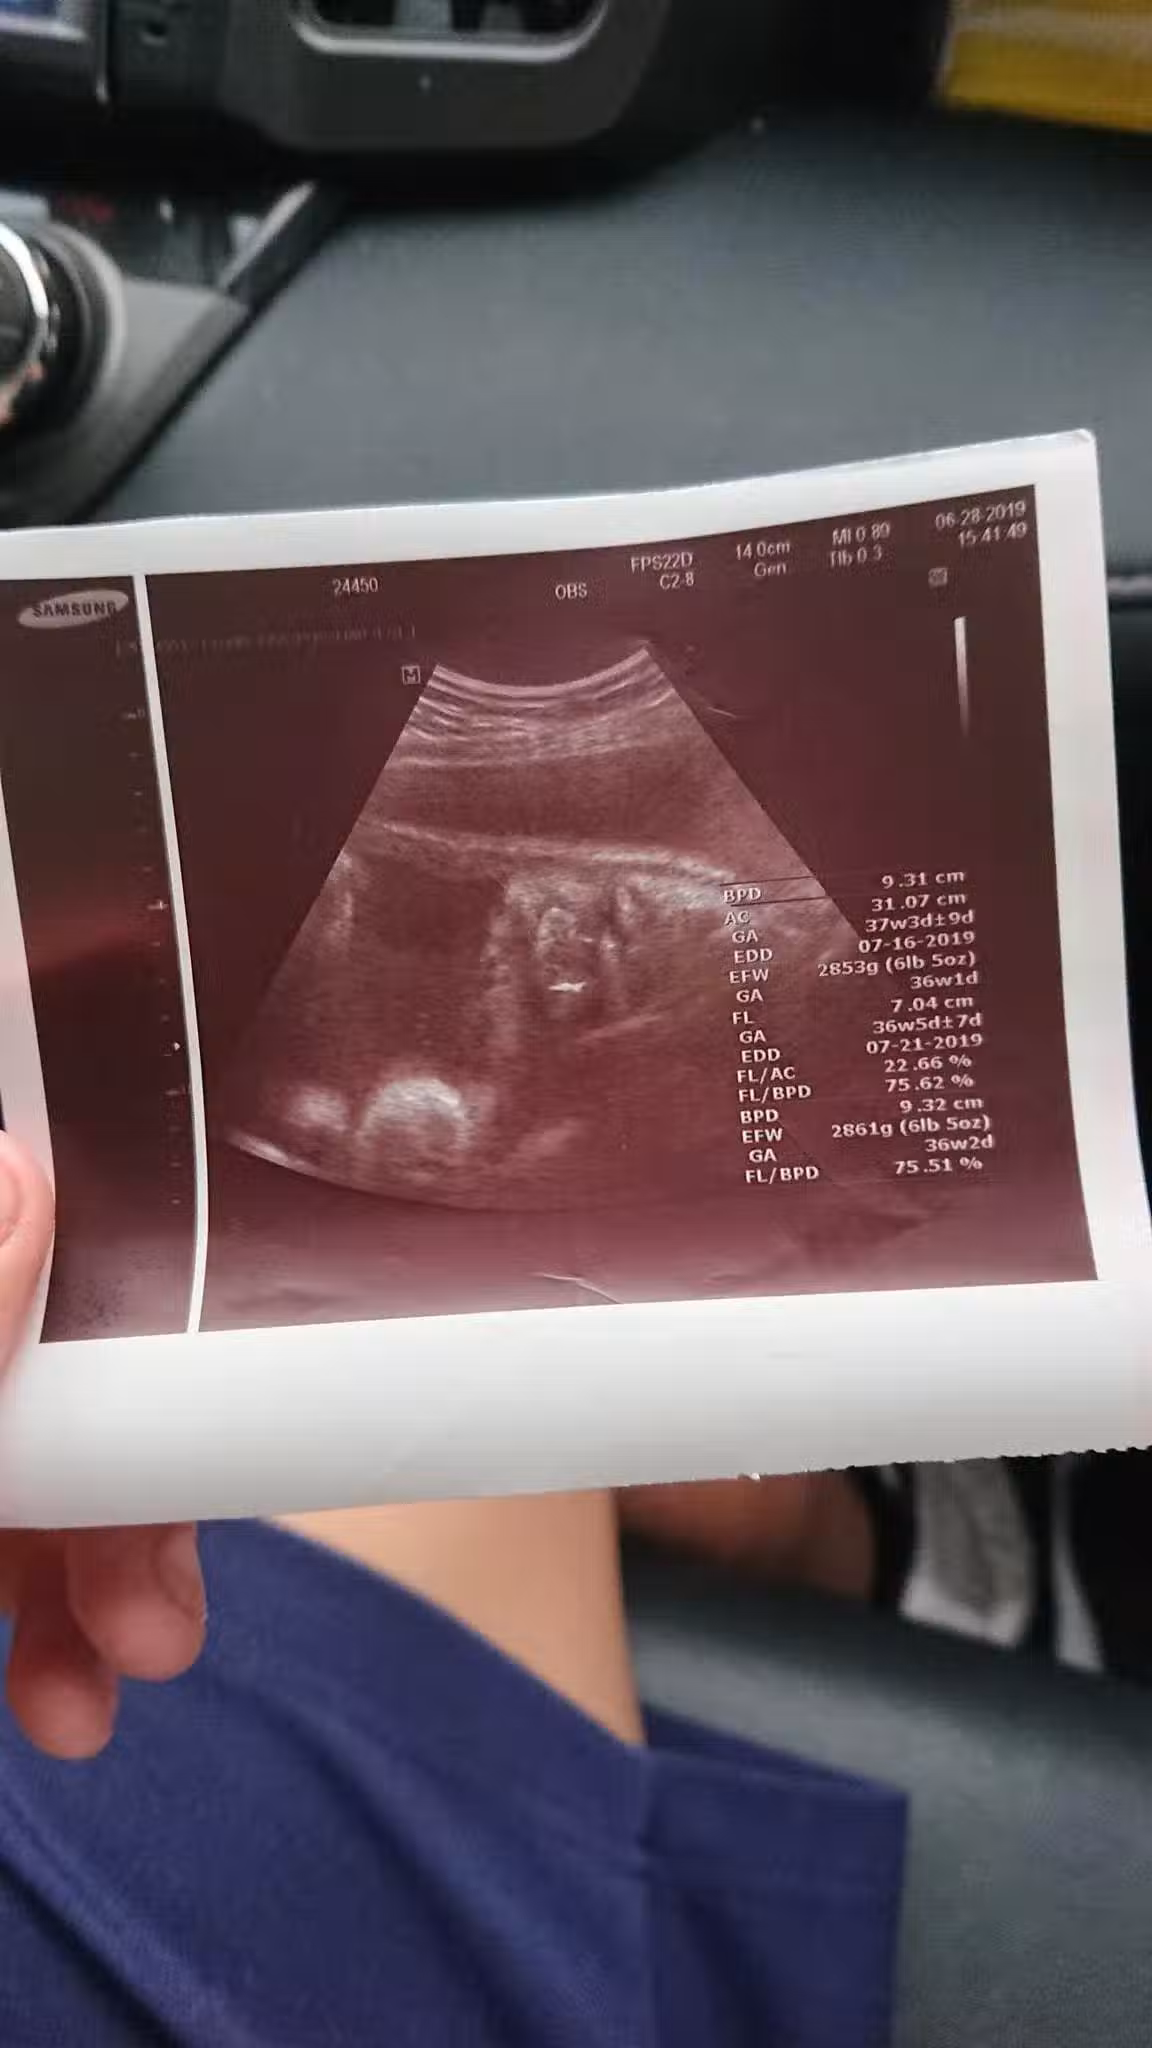

圖片來源:爆怨公社

沒想到兒子女友已經懷孕7個月了,當下他只覺得完蛋了,不知女方家長會怎麼處理,就先帶著高一兒子去見女方家長,還好女方家長很明理,認為事情發生了罵也沒用,就好好讓事情圓滿落幕,由於女方一直不敢告訴家人,所以也沒做產檢,去醫院檢查後,醫生說「胎兒是個男孩,已經約37週大,而且預產期大約在7月中」,所以孩子是一定要生下來的,7月1號時女方再度去醫院,竟然已經開了2指,然後7月2號早上小孩就出生了,原PO看到小孫子很開心也很激動,還自嘲說「在我42歲這年,我當上了阿公,我老婆38歲當了阿嬤,而我兒子竟然只給我們4天的時間心理準備……太刺激的禮物了。」。